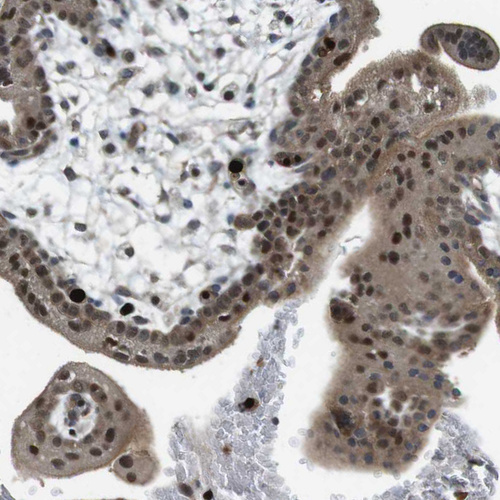

Immunohistochemical staining of human rectum shows strong nuclear positivity in glandular cells.